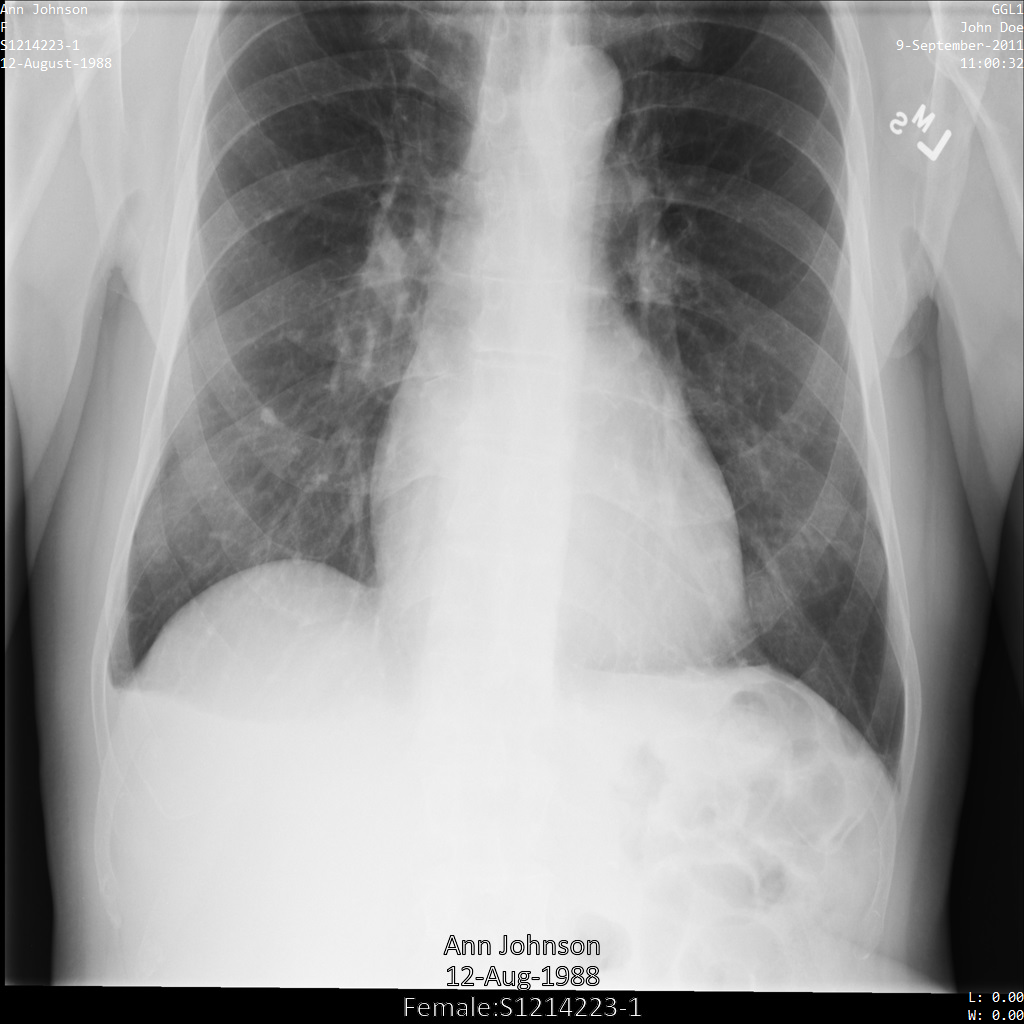

Contoh dalam panduan ini menggunakan satu instance DICOM, tetapi Anda juga dapat menghilangkan identitas beberapa instance.

Setiap bagian berikut memberikan contoh cara melakukan de-identifikasi data DICOM menggunakan berbagai metode. Output gambar yang tidak diidentifikasi disediakan dengan setiap sampel. Setiap sampel menggunakan gambar asli berikut sebagai input:

Anda dapat membandingkan gambar output dari setiap operasi penghapusan identitas dengan gambar asli ini untuk melihat efek operasi.

Setelah mengirimkan gambar ke Cloud Healthcare API, gambar akan muncul seperti berikut. Meskipun metadata yang ditampilkan di sudut atas gambar telah disamarkan, informasi kesehatan terlindungi (PHI) yang tercetak di bagian bawah gambar tetap ada. Untuk juga menghapus teks sisipan, lihat Menyamarkan teks sisipan dari gambar.